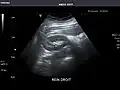

Right kidney